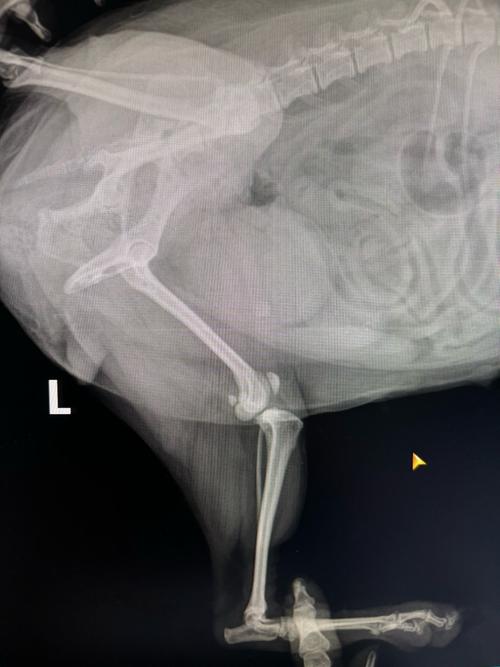

皇家社会官方通报球员伤情,奥德里奥索拉左膝前十字韧带断裂。

根据俱乐部发布的消息,在昨日于阿诺埃塔球场对阵皇家奥维耶多的比赛中,奥德里奥索拉在一次对抗中扭伤左膝。随后,经皇家社会医疗团队详细检查,确认其左膝前十字韧带断裂。目前,手术具体日期尚未最终确定,预计将在未来几天内明确相关安排。

十字韧带损伤是运动员常见伤病之一,通常需要手术治疗并伴随较长的恢复周期。此次受伤预计将对球员后续比赛参与产生一定影响。俱乐部表示,将持续关注奥德里奥索拉的康复进展,并提供必要的医疗支持。